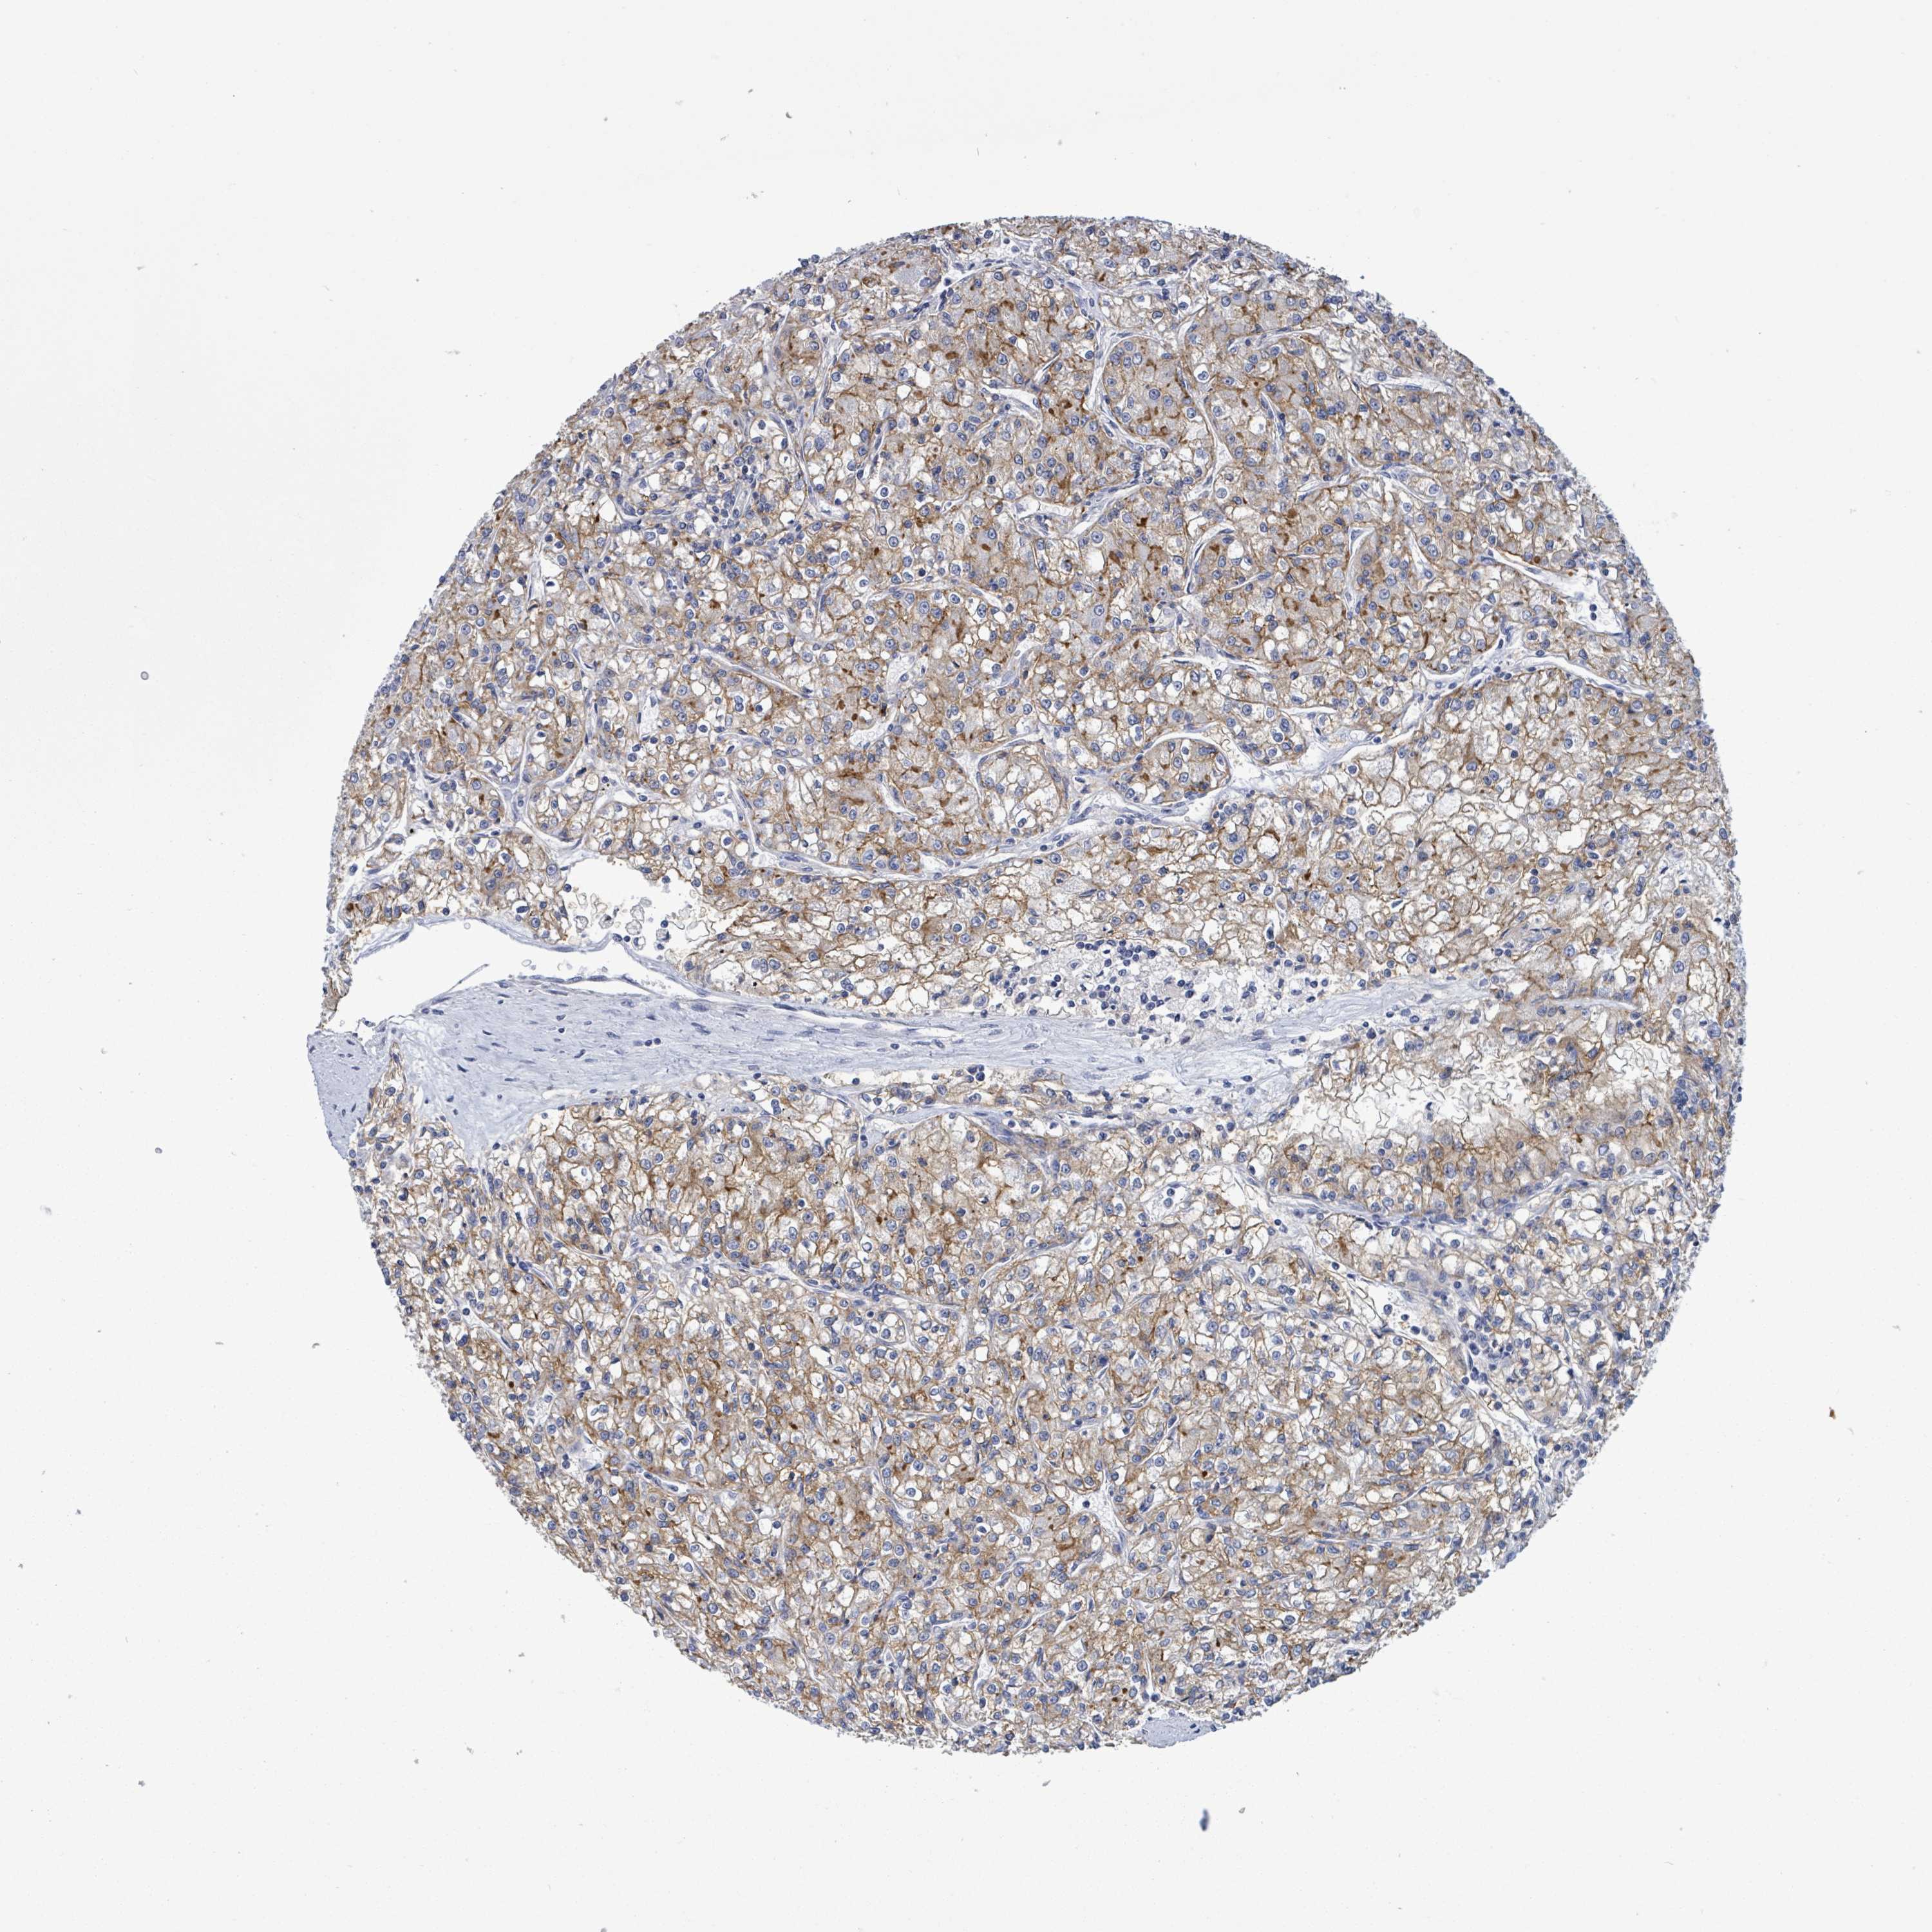

CANCER RENAL CANCER Show tissue menu

KICH TCGA KIRC TCGA KIRC VALIDATION KIRP TCGA PROTEIN RCC CPTAC PROTEIN EXPRESSION

Renal cancer

Kidney chromophobe